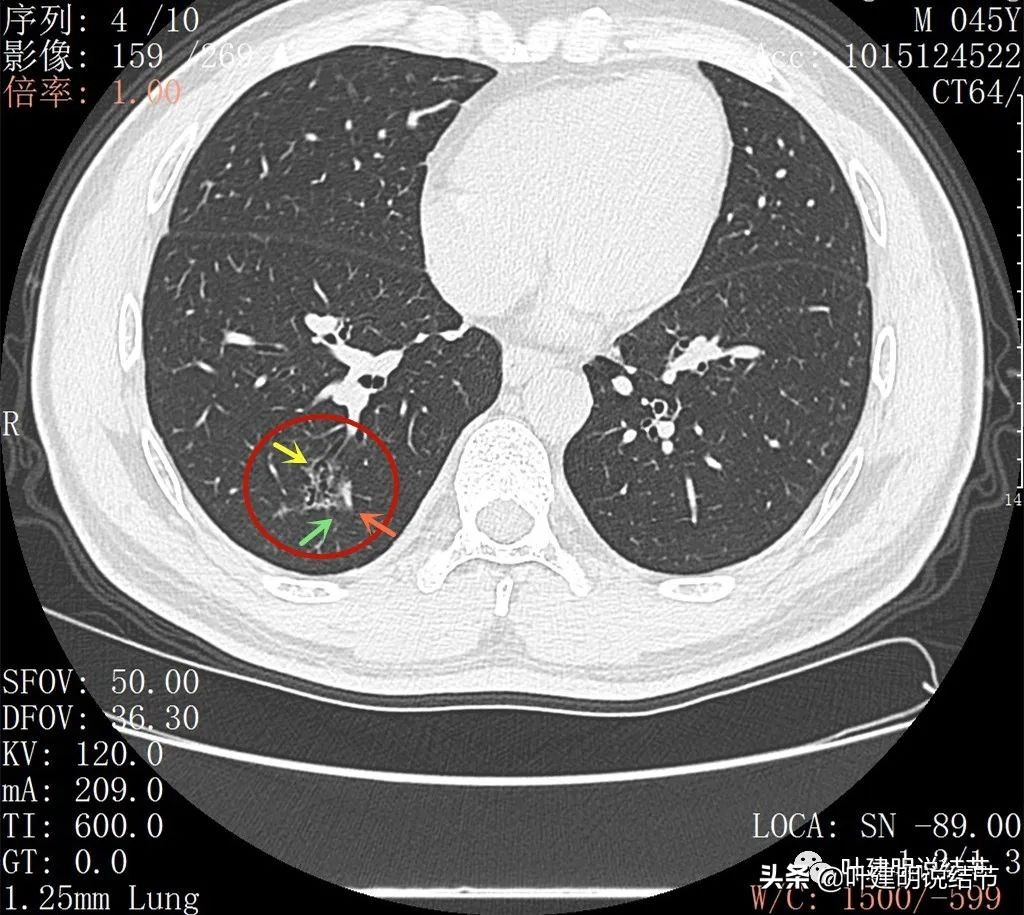

再来看薄层扫描:

病灶感觉很散在,但内部有扩张的细支气管(黄色箭头)、边缘略显不清(绿色箭头),部分有偏实性(粉色箭头)。

边缘血管异常增粗(桔色箭头),边缘显糊(绿色箭头),细支气管扩张(黄色箭头)